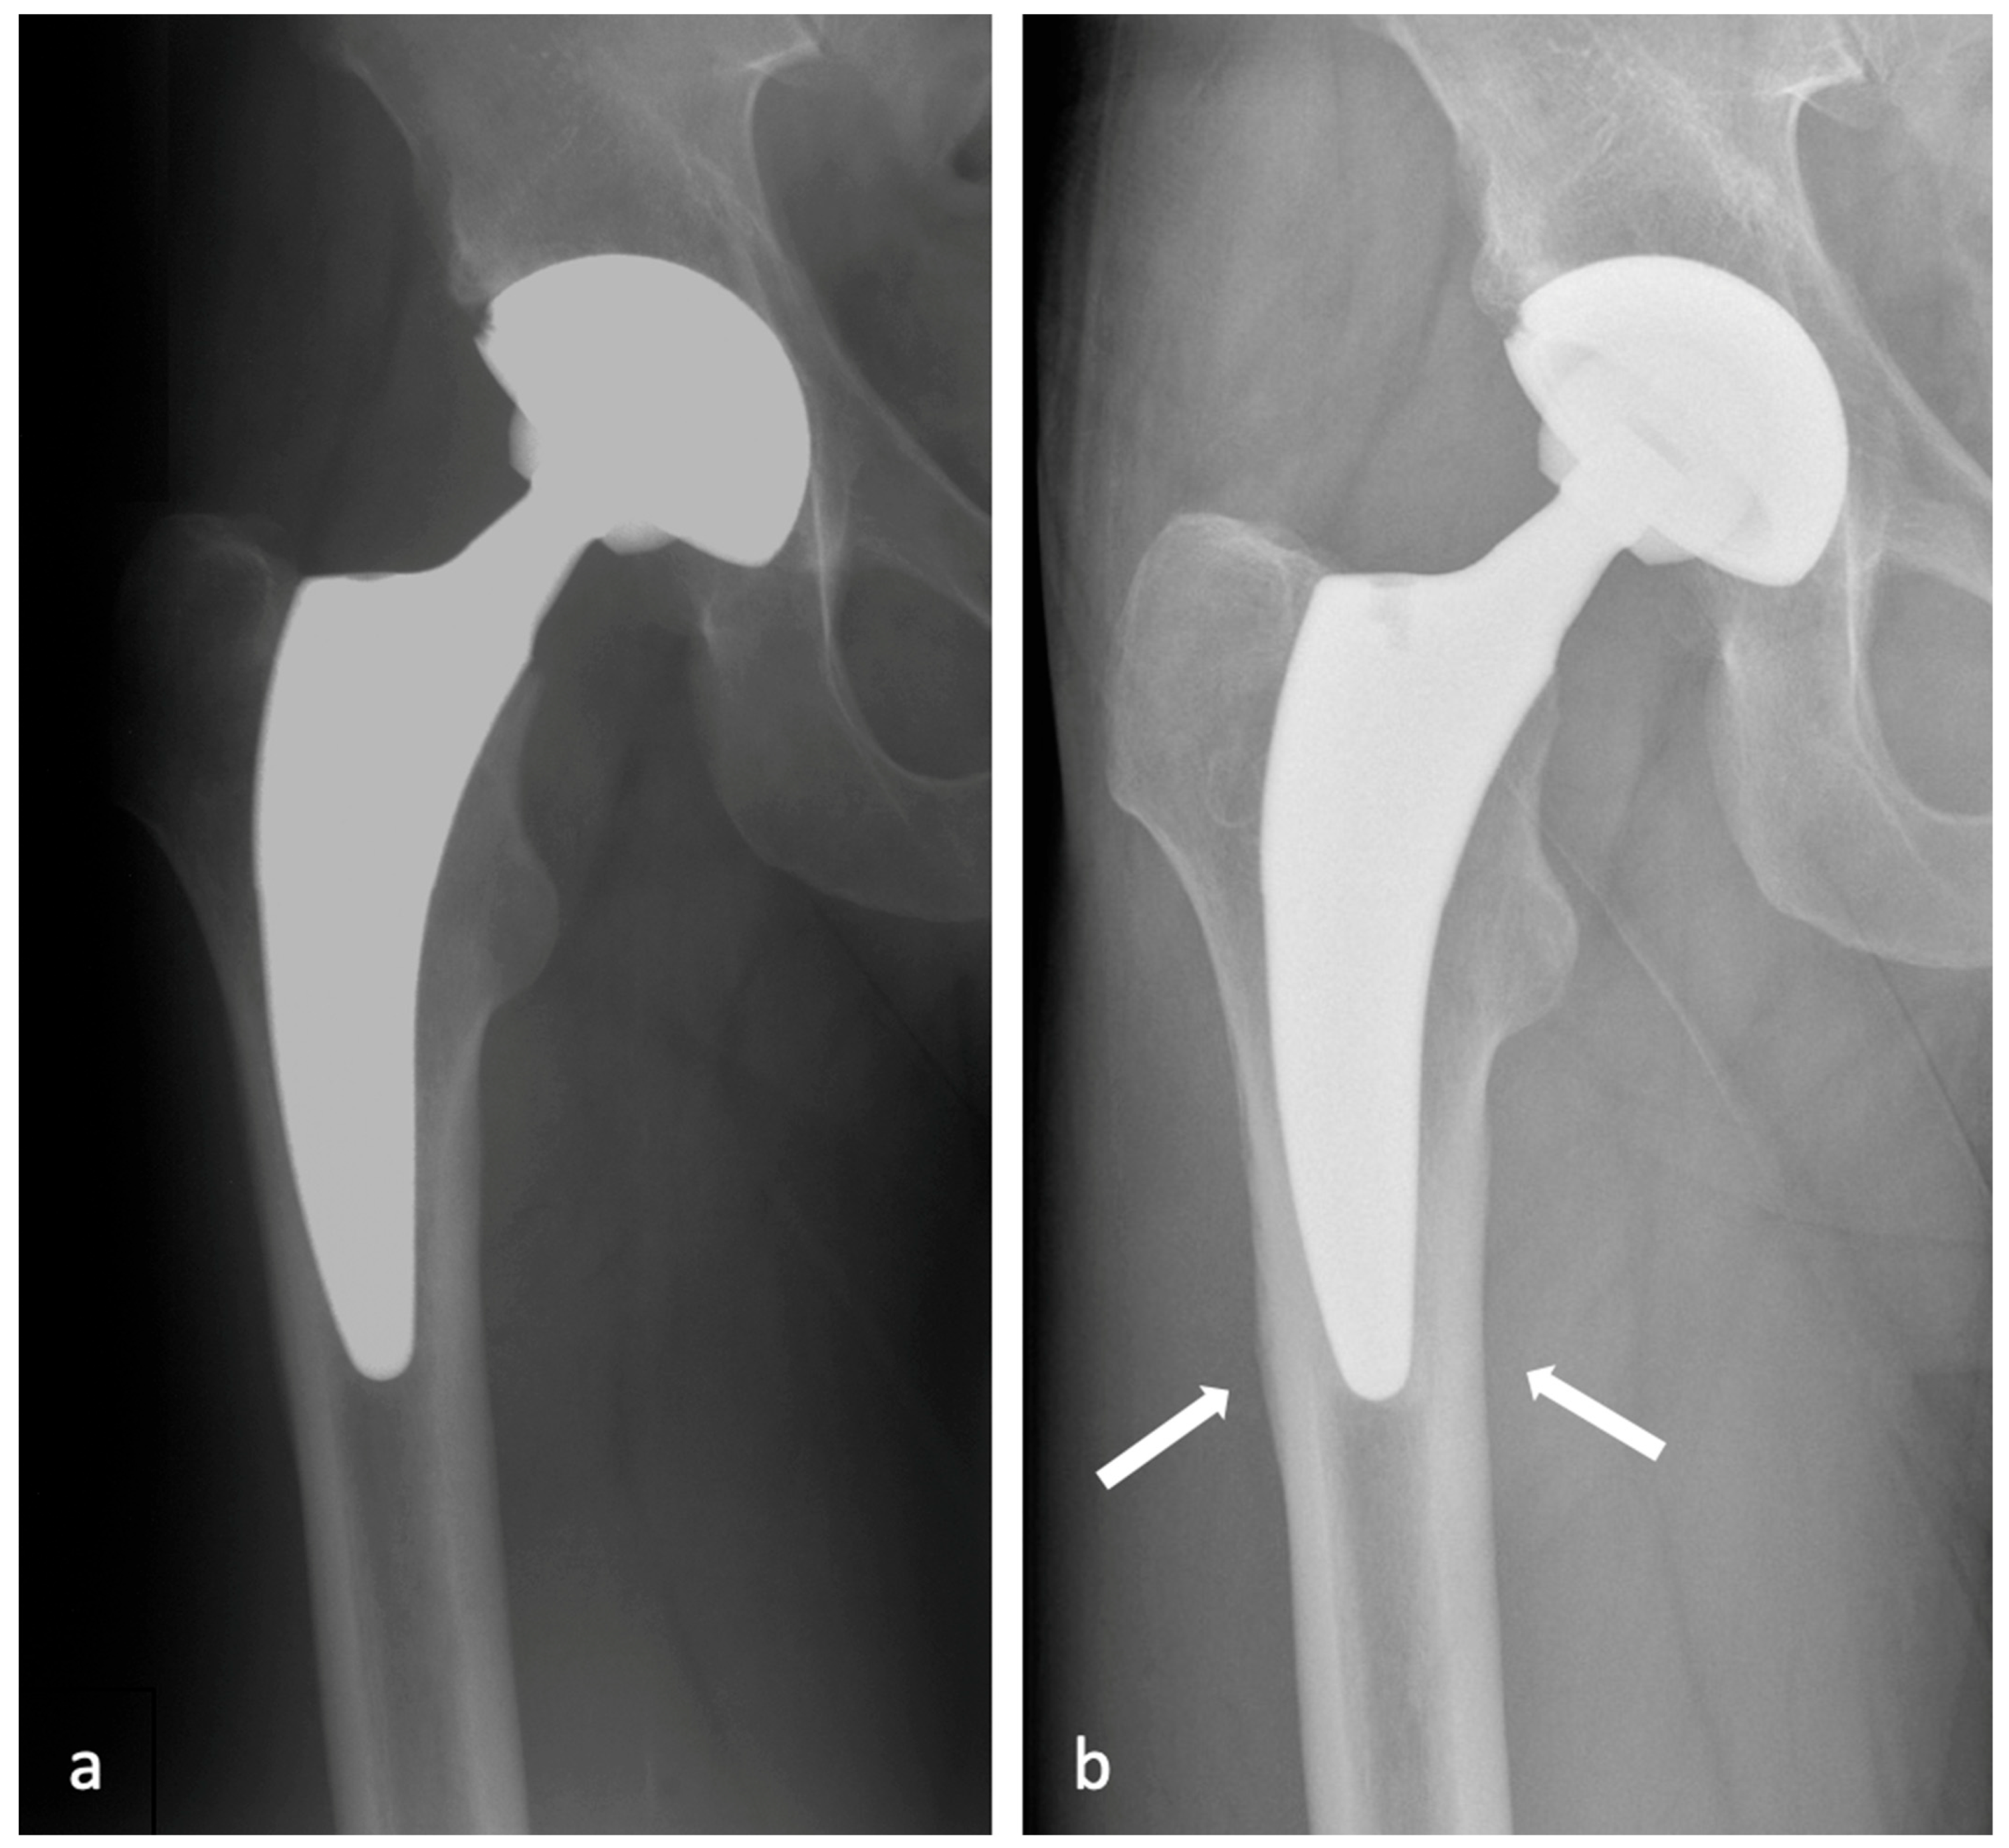

- Innmann, M.M.; Weishorn, J.; Bruckner, T.; Streit, M.R.; Walker, T.; Gotterbarm, T.; Merle, C.; Maier, M.W. Fifty-six percent of proximal femoral cortical hypertrophies 6 to 10 years after Total hip arthroplasty with a short Cementless curved hip stem—A cause for concern? BMC Musculoskelet. Disord. 2019, 20, 261. [Google Scholar] [CrossRef]

- Thalmann, C.; Kempter, P.; Stoffel, K.; Ziswiler, T.; Frigg, A. Prospective 5-year study with 96 short curved Fitmore hip stems shows a high incidence of cortical hypertrophy with no clinical relevance. J. Orthop. Surg. Res. 2019, 14, 156. [Google Scholar] [CrossRef]

- Thalmann, C.; Horn Lang, T.; Bereiter, H.; Clauss, M.; Acklin, Y.P.; Stoffel, K. An excellent 5-year survival rate despite a high incidence of distal femoral cortical hypertrophy in a short hip stem. Hip. Int. 2020, 30, 152–159. [Google Scholar] [CrossRef]